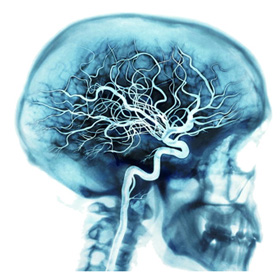

大腦的養份是由體內其中最龐大、最密集的血管網絡所提供。

每下心跳,動脈會輸送百分之 20 至 25 的血液到腦部,而以 10 億計的腦細胞平均消耗血液中約 20% 的氧氣和養份。

而當人在不斷思考及動腦筋的時候,腦部便會大大增加消耗血液中至少 50% 的氧氣和養份。

除動脈之外血管網絡還包括靜脈和微絲血管。